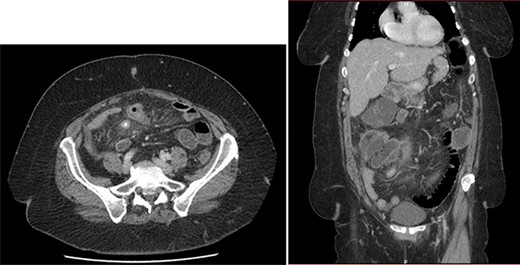

On the sixth post-operative day, the patient suddenly felt weak. She presents with pallor, hypotension and tachycardia. We noticed some blood in the left drain. We immediately started a fluid resuscitation and performed an urgent CT which showed a fresh 6-cm wide splenic sub capsular hematoma associated with a major hemoperitoneum (Fig. 2).